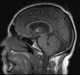

Colloid cyst of third ventricle

A colloid cyst is a non-cancerous tumor in the brain. It consists of a gelatinous material contained within a membrane of epithelial tissue. [Source: Wikipedia ]